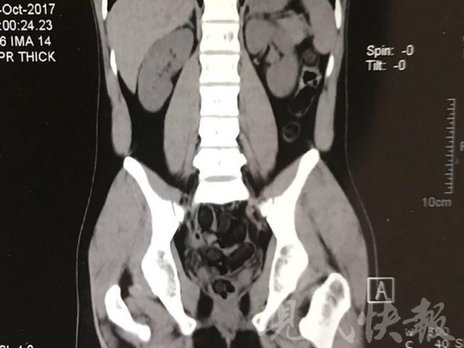

小伙體內(nèi)藏毒300余克 CT掃描圖密密麻麻全是蠶蛹

警方供圖

由于毒品在體內(nèi)一旦泄露有可能致命,警方第一時間將阿永帶到醫(yī)院進行檢查。CT 掃描的結(jié)果顯示,阿永體內(nèi)布滿了密密麻麻的白色圓柱狀固體,就像一粒粒的蠶蛹。在南京市公安局鼓樓分局二板橋派出所,阿永分四次排出了毒品,毛重369.99克。經(jīng)訊問,阿永交代了自己全部的犯罪事實。目前,阿永已被刑事拘留。